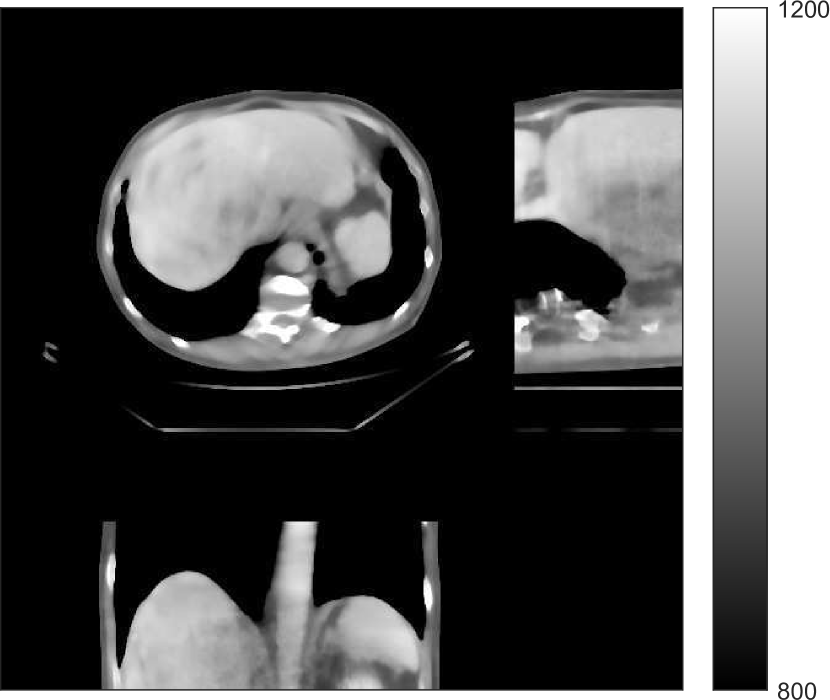

We used the pre-learned union of 15 square transforms from the XCAT phantom simulations to reconstruct the synthesized helical chest scan volume of size 420×420×222420420222{420\times 420\times 222} with Δx=Δy=1.1667subscriptΔ𝑥subscriptΔ𝑦1.1667\Delta_{x}=\Delta_{y}=1.1667 mm and Δz=0.625subscriptΔ𝑧0.625{\Delta_{z}=0.625} mm. The sinograms were of size 888×64×3611888643611888\times 64\times 3611. Since the clinical data is synthesized via the PWLS-ULTRA reconstruction, the noise model for this synthesized data is obscure, making it difficult to determine appropriate low-dose levels for such data. We tested the radiation dose of I0=1×104subscript𝐼01superscript104I_{0}=1\times 10^{4} with an electronic noise variance the same as the XCAT phantom simulation, i.e., σ2=25superscript𝜎225\sigma^{2}=25. The percentage of non-positive pre-log measurements for the synthesized clinical data in this case was around 0.14%percent0.140.14\%. Such non-positive values were replaced by 1×1051superscript1051\times 10^{-5} for PWLS-based methods. Fig. 8(a) shows the “true” clinical image that was reconstructed from real clinical regular-dose sinogram using the PWLS-ULTRA method.

Refer to caption

(a)

(b)

Figure 8: (a) “true” clinical image (HU), (b) the reconstruction (HU) of the synthesized data with PWLS-EP for I0=1×104subscript𝐼01superscript104I_{0}=1\times 10^{4} with βep=215subscript𝛽𝑒𝑝superscript215\beta_{ep}=2^{15}. The central axial, sagittal, and coronal slices of the volume are shown.

Similar to the XCAT phantom simulation, the initial image for both SPULTRA and PWLS-ULTRA was a reconstruction obtained using PWLS-EP. We set the regularizer parameter βepsubscript𝛽𝑒𝑝\beta_{ep} for PWLS-EP to 215superscript2152^{15} to generate a smoother (with less noise) initial image, which led to good visual image equality for the SPULTRA and PWLS-ULTRA reconstructions. Since the optimization problem for PWLS-EP is strictly convex, we simply initialized PWLS-EP with a zero image. Fig. 8(b) shows the PWLS-EP reconstructed image for I0=1×104subscript𝐼01superscript104I_{0}=1\times 10^{4}. We set the regularizer parameters for both PWLS-ULTRA and SPULTRA as γc=5×104subscript𝛾𝑐5superscript104\gamma_{c}=5\times 10^{-4}, and β=1.5×104𝛽1.5superscript104\beta=1.5\times 10^{4}.